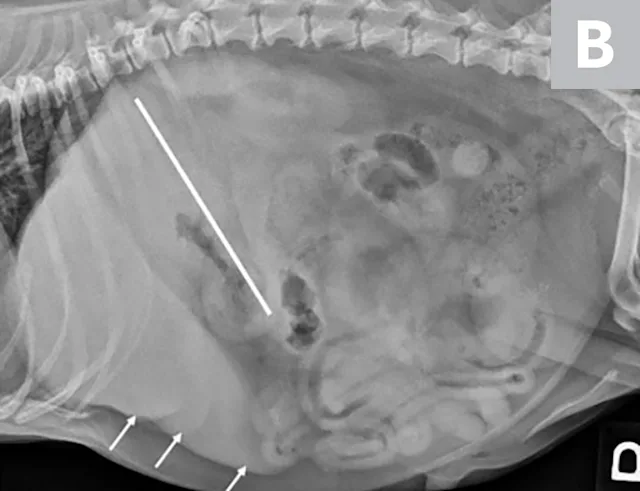

Imaging of a 1-year-old neutered male standard poodle presented with anorexia, lethargy, vomiting, hypoalbuminemia, hypoproteinemia, and cranial abdominal organomegaly. Transverse (A) and sagittal (B) ultrasound of the liver and gallbladder (GB). The liver is enlarged (with increased distance off the stomach from the diaphragm, rounded borders, and extension ventral to the stomach), diffusely hyperechoic, and homogenous. The gallbladder is moderately distended with a normal wall and content. Radiographs demonstrate hepatomegaly and splenomegaly (C). Abdominal ultrasound images revealed splenic enlargement with a mildly mottled architecture and a solitary hypoechoic nodule (D; arrowheads). The pancreas is enlarged and lobulated with multiple hypoechoic tracts and a peripheral capsule (E; between electronic cursors [X’s]). The jejunal lymph nodes are severely enlarged (F; between electronic cursors [X’s]), more than expected for a young dog. The combination of severe hepatosplenomegaly and lymphadenomegaly make systemic disease (eg, infectious, neoplastic) most likely. The appearance of the pancreas is due to pancreatic edema secondary to hypoproteinemia. Acute liver injury was diagnosed, and lymphoma was diagnosed based on hepatic and splenic cytology.